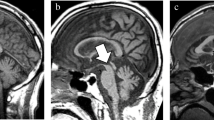

Patient 11: 65-year-old female with CBDS with right predominant rigidity, right pyramidal signs and right limb kinetic apraxia. a, b FLAIR (TR/TE/TI 8,802/147.1/2,200 ms) images show left frontoparietal cerebral atrophy. Hyperintense areas are apparent in the subcortical white matter in the left precentral gyrus (arrows) and less intensely in the postcental gyrus (arrowhead). c ECD-SPECT images show decreased perfusion in the left frontoparietal lobes and in the left putamen

Patient 16: 71-year-old male with CBDS with right rigidity and right apraxia. a FLAIR (TR/TE/TI 8,802/147.1/2,200 ms) image shows atrophy in the left frontoparietal lobes and faint hyperintense lesions in the subcortical white matter in the left precentral gyrus (arrow). b FLAIR image demonstrates subtle hyperintensities in the operculum (arrow). This image is the lowest section in which hyperintensities were observed (AAR anterior ascending ramus of the sylvian fissure, prC precentral sulcus, cs central sulcus, ics insular central sulcus). c, d T2-weighted (TR/TE 4,000/99 ms) images show unilateral atrophy in the left cerebral peduncle (c, arrow) and pyramid (d, arrow) without signal intensity changes. In this patient, unilateral atrophy in the cerebral peduncle is the most outstanding finding of the CBDS

Patient 2: 62-year-old female with CBDS with left dominant rigidity, left pyramidal signs and right frontal and parietal lobe signs. a Surface anatomy scan (TR/TE 1,529/185 ms) image shows atrophy of the right precentral (prC) and postcentral (poC) gyri. b Midsagittal T1-weighted (TR/TE 400/10 ms) image shows atrophy of the corpus callosum (arrowhead) and midbrain tegmentum (arrow)

Atrophy in the cerebral peduncle was observed in seven patients in six of whom the atrophy was ipsilateral to the dominant atrophic cerebral hemisphere (Fig. 2c). All of the seven patients showed contralateral pyramidal signs. No signal intensity changes were noted in the cerebral peduncles. In patient 16, atrophy in the cerebral peduncle was the most outstanding imaging finding of CBDS (Fig. 2c). Atrophy in the pyramid ipsilateral to the clinically more affected cortices was observed in five patients (Fig. 2d). Four of the five patients also showed atrophy in the cerebral peduncle on the same side. Atrophy in the midbrain tegmentum was seen in eight patients (Fig. 3b). Among them, three patients showed vertical gaze palsy. Atrophy in the corpus callosum was observed in 15 patients (94%) (Fig. 3b).

On FLAIR images, increased signal intensity changes were noted in the frontal and/or parietal subcortical white matter in 14 patients (88%) (Figs. 1 and 2). The side of the hyperintense areas was ipsilateral to the clinically more affected cortices in 13 patients. In the contralateral sides, more subtle hyperintensities were occasionally observed. In the rolandic region, hyperintense lesions were observed in 13 patients. Hyperintense areas were more frequently observed in the upper sections in which the superior frontal sulcus was well visualized compared with the lower sections. The operculum was the lowest space in which hyperintense lesions were observed on FLAIR images (Fig. 2b). Motor aphasia with apraxia of speech, forced grasping reflex, and motor impersistence of eye closing and tongue protrusion were frontal signs. The MR images of seven of eight patients with the frontal signs showed hyperintensities in the frontal lobes. The MR images of two of four patients with parietal signs (cortical sensor loss and limb kinetic apraxia) showed hyperintensities in the parietal lobe.

Unilateral atrophy in the cerebral peduncle was observed in seven patients. None of the atrophy was accompanied by signal changes in the corticospinal tract (CST) in the cerebral peduncle. The side of atrophy was contralateral to pyramidal signs in all of the seven patients. In a review article, Boeve et al. [1] reported that asymmetric atrophy in the cerebral peduncle might be present in patients with CBDS. However, no images were presented. The cerebral peduncle consists of descending corticofugal fibers [10]. Neuronal degeneration in the posterior frontal and parietal lobes in CBD induces secondary degeneration in the corticospinal, corticobulbar and parietopontine fibers, and consequently there is atrophy in the cerebral peduncle on the affected side. The reason why signal intensity changes in the CST are not associated with atrophy in the cerebral peduncle is unknown. However, the slow progression of neuronal degeneration in CBD might be a reason. Recently, a histopathological study of the autopsy examinations of ten patients with CBD revealed constant and severe involvement of Betz cells in the primary motor cortex and degeneration of the CST [11]. Furthermore, Boelmans et al. [12] demonstrated CST atrophy in a patient with CBDS using tractography. Therefore, when unilateral atrophy in the cerebral peduncle without signal intensity changes in the CST is observed on MR images of patients with asymmetric parkinsonism, higher cortical dysfunction and dementia, CBDS might be a major consideration in the differential diagnosis.

Atrophy of the midbrain tegmentum was observed on sagittal images in eight patients. It was not uncommon that patients with CBDS developed supranuclear gaze palsies that were not distinguishable from those seen in PSP [1]. Atrophy of the midbrain tegmentum on MR images has also been observed in PSP patients [13, 14]. We did not find any difference in atrophy of the tegmentum between PSP and CBDS patients. Thus, atrophy of the midbrain tegmentum was not unique to PSP patients, but is also seen in CBDS patients.

Doi et al. [15] reported a patient with pathologically confirmed CBD. T2-W images of the patient showed focal atrophy of the bilateral frontal cortex and asymmetric regional hyperintensities of the subjacent white matter in the frontal lobe with greater prominence contralateral to the side more severely affected clinically. They concluded that these signal changes seemed to primarily reflect the progression of neuronal degeneration, especially the demyelination secondary to axonal loss or change. Although they described only one patient and used T2-W imaging, the hyperintensities in the subcortical white matter are consistent with our findings on FLAIR images. Moreover, Winkelmann et al. [16] reported two patients with CBDS in whom MR images demonstrated T2 elongation in the rolandic region.

Mirra and Hyman [17] note that the neuropathological features of CBD include an often asymmetric cortical atrophy, predominantly involving the perirolandic cortex, but also involving other cortical regions and the underlying white matter showing considerable loss of myelin and even axons. Therefore, we agree with the conclusions of Doi et al. [15] that these signal abnormalities reflect progression of neuronal degeneration, especially demyelination secondary to axonal loss or change. Moreover, we believe it is unique to CBDS that FLAIR images showed hyperintensities in the rolandic region with asymmetric atrophy with the predominance contralateral to the side clinically more severely affected. To the best of our knowledge, these hyperintensities have never been reported in patients with AD, PSP, FTD, Pick disease or Lewy body disease. We evaluated the hyperintensities in the cerebral subcortical white matter mainly on FLAIR images, because FLAIR images were more sensitive than T2-W images in showing lesions in the subcortical white matter.